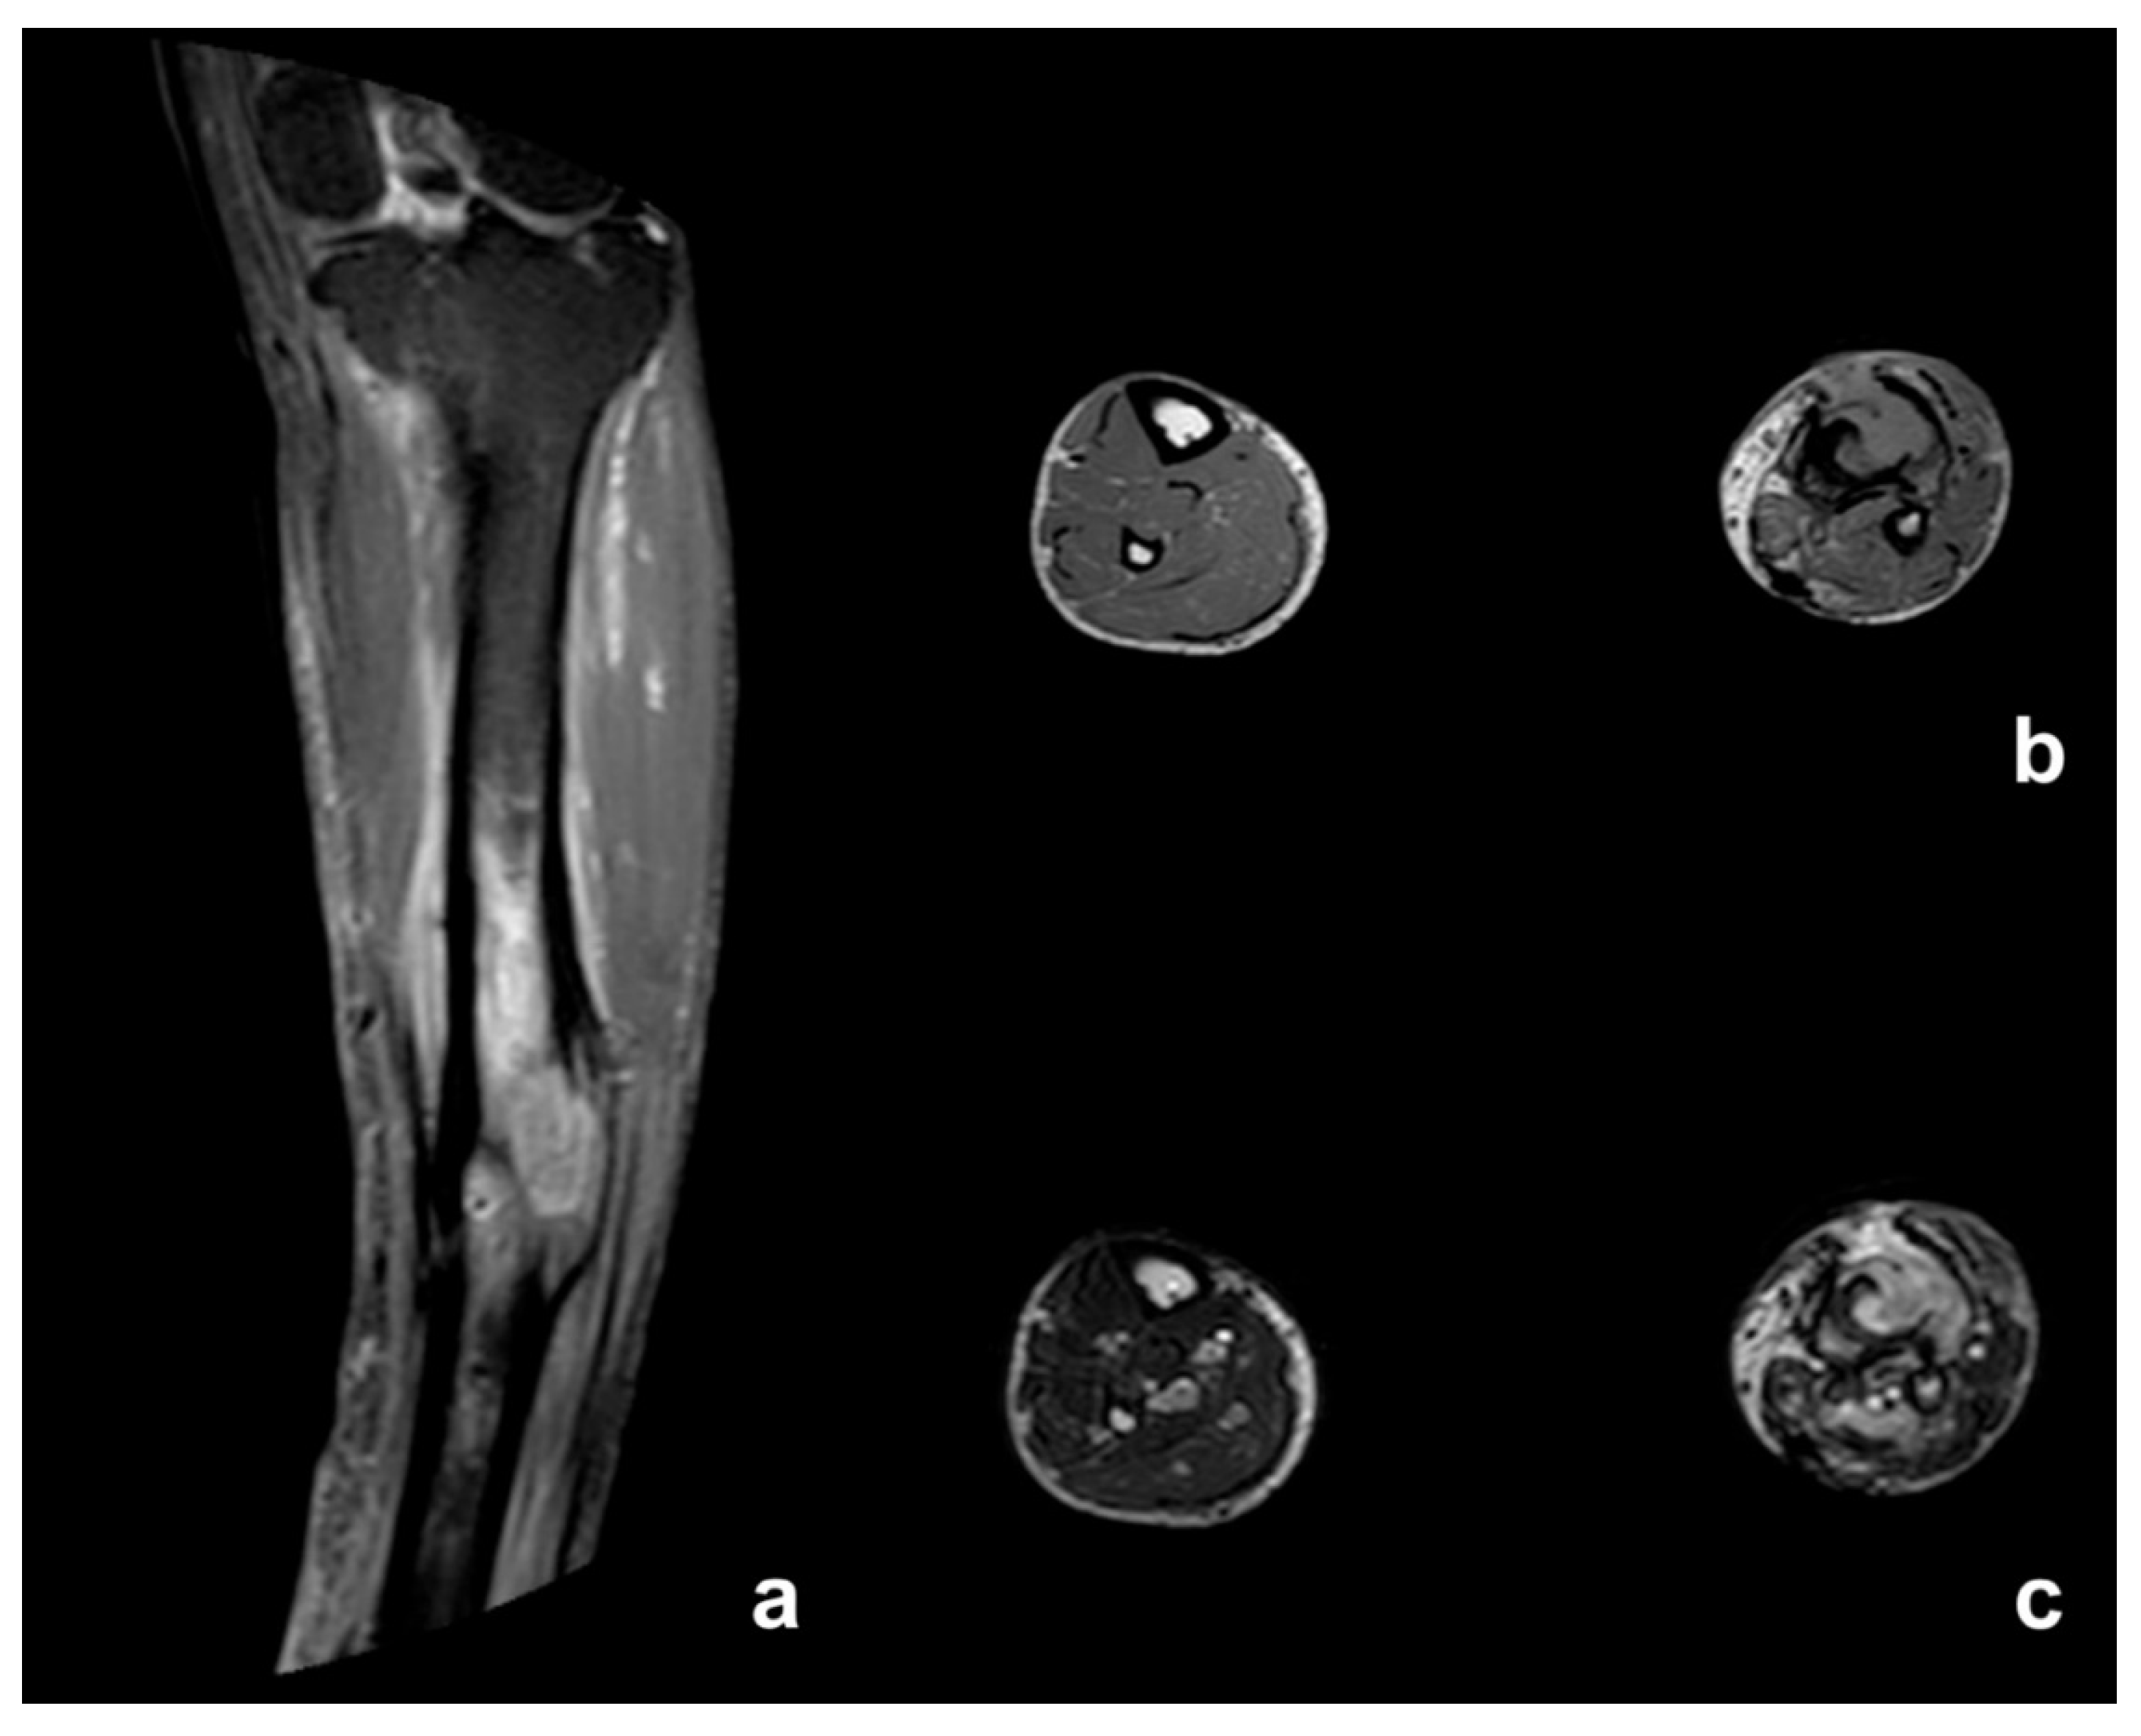

| MRI Signal | Diagnosis | |||||

|---|---|---|---|---|---|---|

| T1 | Stir | T1 MoC | AO | CO | SCC | |

| Bone Marrow Edema | Low | High | High (Increased) | Common | Less common # | =CO |

| Intraosseous abscess | Low | High | Peripheral Enhancement | Uncommon | Uncommon # | =CO |

| Cortical bone | Low | Low | No Enhancement | Normal or Periosteal Elevation | Thickened, extensive remodeling | =CO |

| Sinus tract | Low | High | Peripheral Enhancement | Never | Very common | Always |

| Sequestrum | Low | Low | Peripheral Enhancement | Never | Less Common | =CO |

| Extraosseous soft tissue changes | Low | High | Enhancement | Very common | Less Common * | Mass developing in the epithelial tract of the fistula |